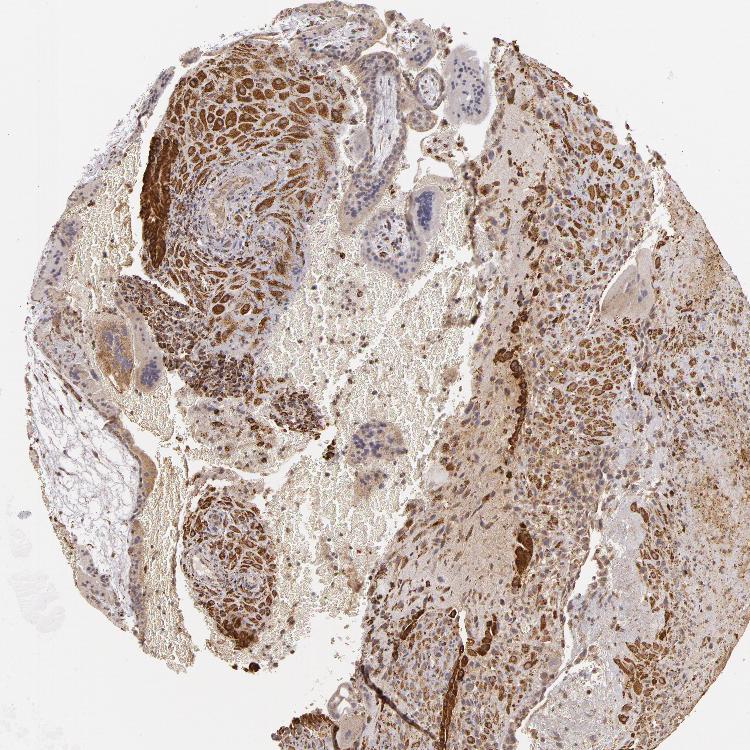

PLACENTA